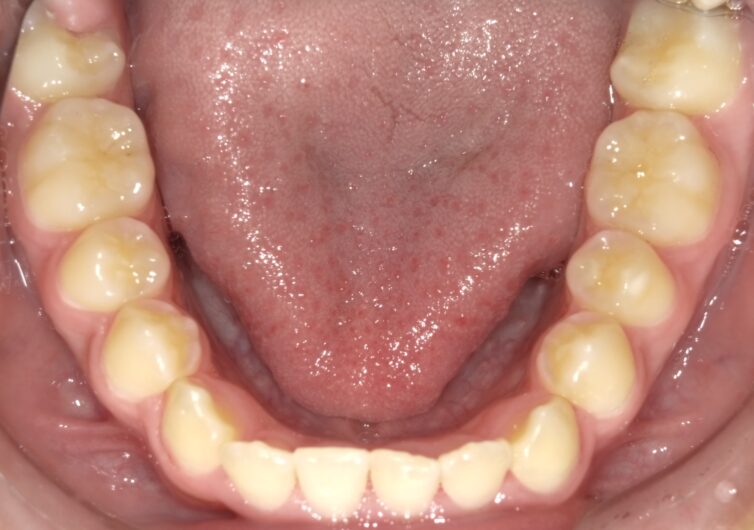

■ 治療経過(約3年間)

・上顎の幅径の改善

・前歯部の反対咬合の解消

・上下顎の前後的バランスの改善

成長を利用しながら、無理のない矯正を行うことで、

永久歯が自然に並ぶ環境を整えることができました。

■ 治療結果

3年の経過で反対咬合は改善し、

現在は安定した咬合関係を維持しています。

現時点では、

本格的なワイヤー矯正(2期治療)の必要性は低いと判断しています。